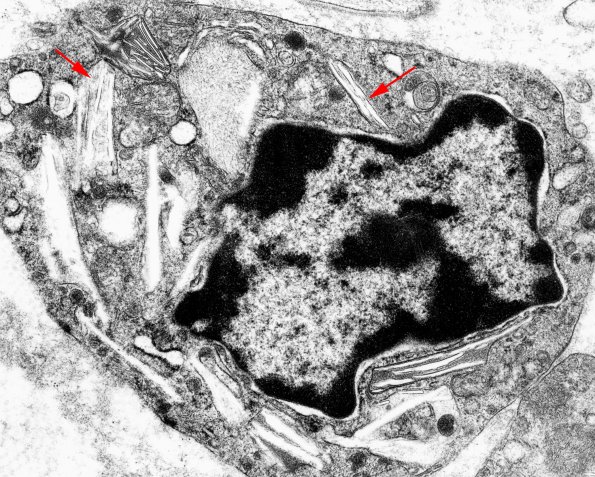

Although only a few inclusions are seen in plastic sections, straight inclusions (arrows) are seen in macrophage and Schwann cells. (electron micrograph) (Thanks to JM Bilbao for the image)